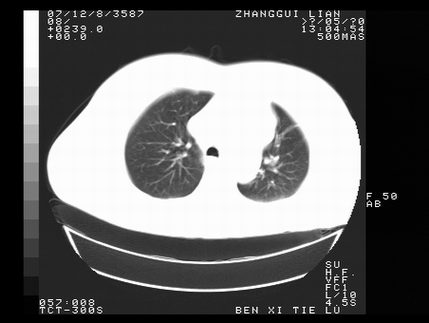

标题: CT10818:男,73,TB病史,现病史肺炎及直肠CANCER术后 [打印本页]

标题: CT10818:男,73,TB病史,现病史肺炎及直肠CANCER术后

左侧中央型肺癌伴阻塞性肺炎\\不张,左侧前上纵隔亦增宽,建议上传纵隔窗除外淋巴结转移.

考虑:左侧中央型肺癌伴阻塞性肺炎,纵隔淋巴结转移。

1)考虑为:左侧中央型肺癌伴阻塞性肺炎,纵隔淋巴结转移。2)双侧少量胸腔积液。3)心包积液。

左侧中央型肺癌伴阻塞性肺炎,纵隔淋巴结转移。

考虑左侧中央型肺癌伴阻塞性肺炎,纵隔淋巴结转移。